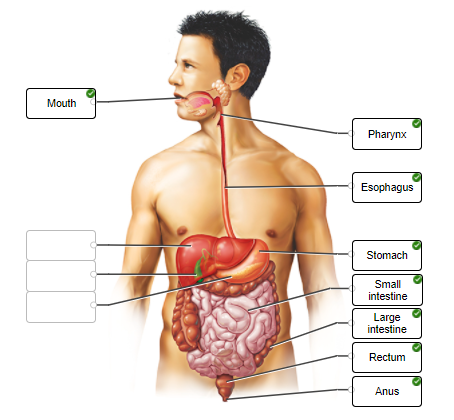

Label only the organs of the digestive system that comprise the alimentary tract.

Before looking at diagnostic images, take a moment to identify digestive organs in the illustration.